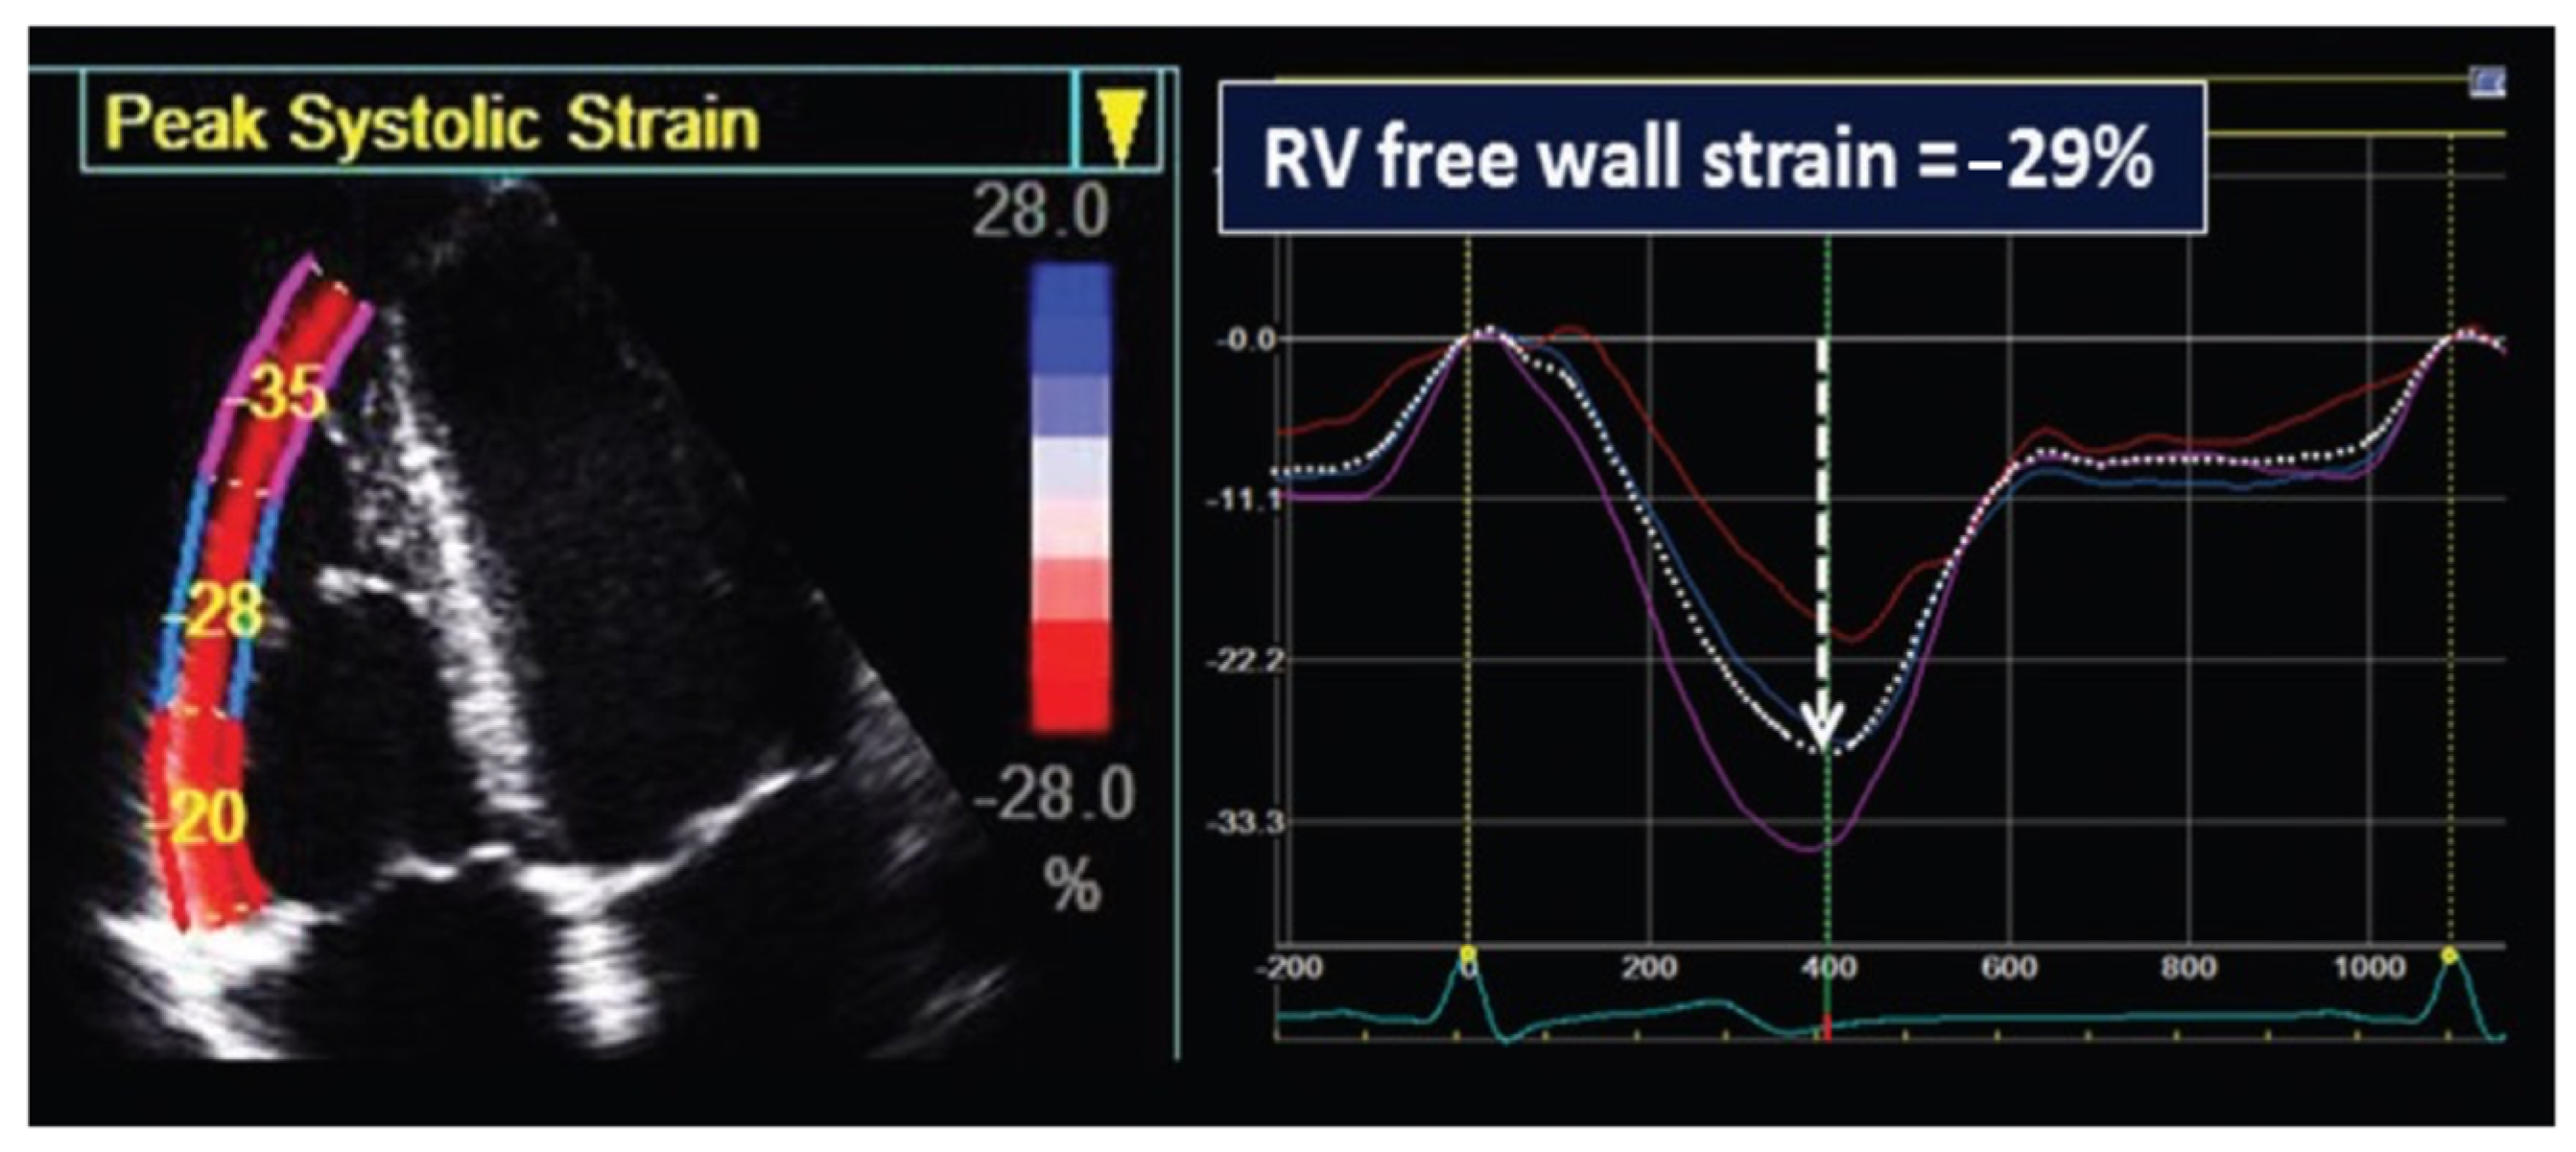

| 2D STE | |||

| RVFWSL (%) | −22.8 ± 5.5 | −25.3 ± 6.3 | 0.18 |

| Basal (%) | −23.0 ± 6.5 | −23.1 ± 6.2 | 0.95 |

| Mid (%) | −24.0 ± 6.7 | −26.3 ± 8.0 | 0.33 |

| Apical (%) | −21.4 ± 7.5 | −26.6 ± 7.5 | 0.03 |